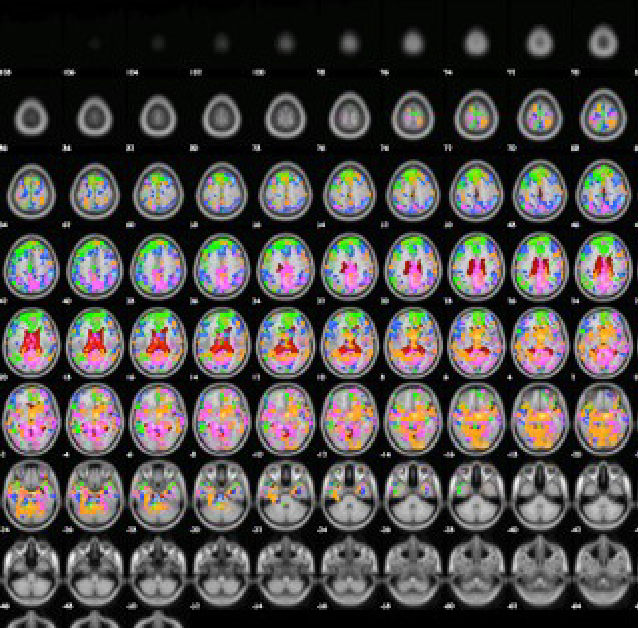

rs-fMRI(resting state fMRI)​

安静時における脳の神経活動を測定する技術です。脳領域間における機能的結合や安静時の神経活動(デフォルトモードネットワークなど)の観察に用いられています。

神経科学や心理学、臨床医学など多くの研究に利用されています。​

安静時における脳領域間の機能的結合を評価しています。(Functional Connectivity)

​アカゲザルの特定の脳領域(**)に対して相関がある脳領域を評価しています。​